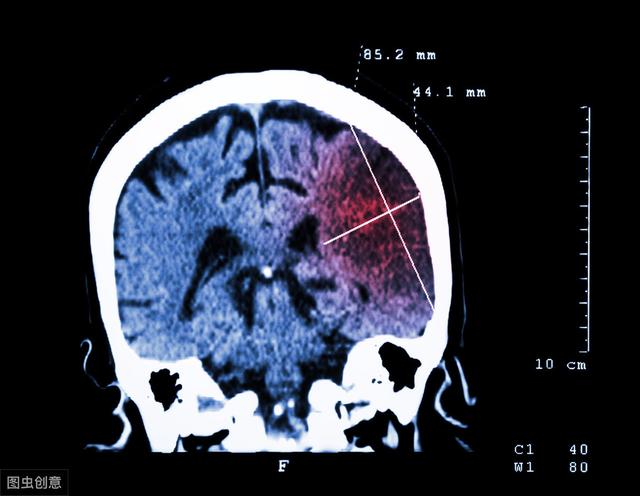

脑梗 , 指的是脑部血管发生堵塞 , 血液供应得不到不保障 , 从而导致脑血管缺血、缺氧 , 诱发局部脑组织坏死 。

据数据统计 , 全球每年新生脑梗患者高达2000万人 , 而我国就占有300万 。 仅有16%的脑梗患者能够得到准确及时的治疗 。